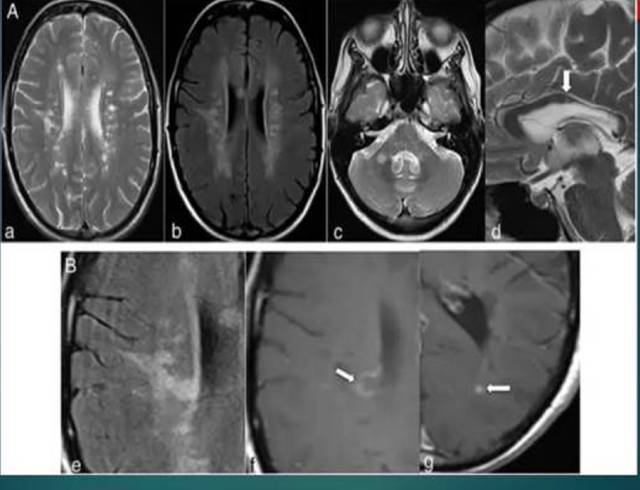

3. 把“多发性硬化”误认为腔梗

文章插图

多发性硬化主要见于年轻人 , 在 CT 上表现为低密度 , 病灶特点为直角征(病变的横轴与正中线和侧脑室体部垂直)、煎蛋征(做 CT 增强有所体现);腔梗多见于老年人 , 区别多发性硬化除了影响诊断 , 要从病史、临床表现、查体上进行鉴别 。

4. 把“脑白质疏松” 误认为腔梗影像

脑白质疏松(即脑白质脱髓鞘)常与腔梗相伴随 , 基本上在侧脑室体旁融合成片 , 侧脑室的前角后角较多见 。